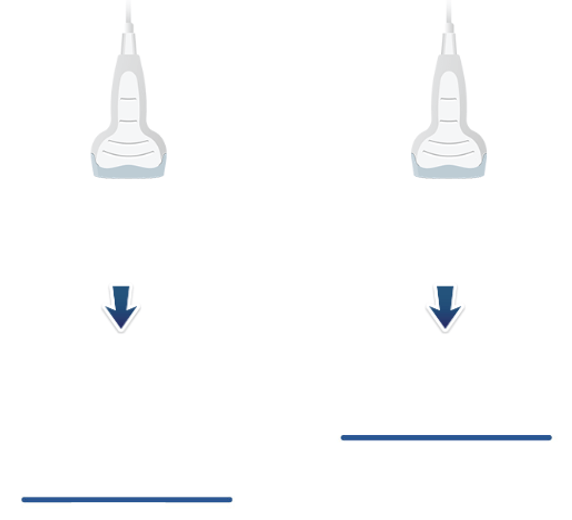

Select / Change Probes

When the system is turned on, it is very important to select the right probe for the right type of exam. The transducer head has an imprint area, where the sound waves leave and return to the transducer. It is this area of the transducer footprint that must remain in contact with the body to transmit and receive ultrasonic waves. Each transducer has a probe to help identify its orientation. Transducers are manufactured in a range of shapes, sizes, and frequencies and are suitable for specific clinical applications.